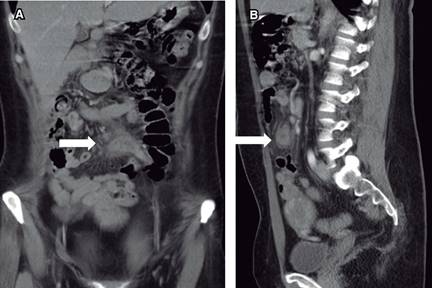

Figura 2: Imagen de tomografía computarizada de abdomen mostrando en corte coronal (A) y corte sagital (B) al apéndice cecal fase edematosa/supurativa, localizada en mesogastrio, cambios inflamatorios de la grasa mesentérica adyacente (flecha blanca).